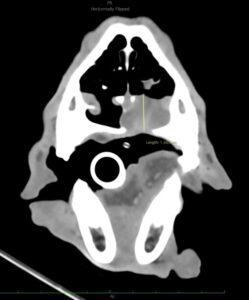

Dos semanas más tarde se realiza el TC de reestadiaje y se detecta la presencia de enfermedad metastásica en pulmón. Adicionalmente, la afectación completa del paladar y la invasión en cavidad nasal hacen que se descarte la cirugía como terapia local.

En el momento del estadiaje inicial, el paciente presenta un buen estado general, pero se evidencia el crecimiento de la lesión primaria y la existencia de metástasis regionales y a distancia según TC. Se administra la segunda dosis de la vacuna de melanoma y se planifica radioterapia paliativa, seguida de quimioterapia adyuvante con carboplatino. Cuatro semanas más tarde se completa la radioterapia paliativa en cinco sesiones (22.5Gy) dirigida al melanoma oral y metástasis en ganglios linfáticos mandibulares y retrofaríngeos bilaterales. Los cuidadores rechazan finalmente el tratamiento con carboplatino adyuvante.

A los 18 meses del diagnóstico, los cuidadores refieren la aparición de hifema y exoftalmia en el ojo derecho, lo que sugiere metástasis, además de una masa perianal compatible con neoplasia indiferenciada (posible melanoma amelanótico). En el estudio de TC se documenta una respuesta completa de la lesión primaria y metástasis nodales y una remisión casi completa de las metástasis pulmonares (lesiones milimétricas equívocas) (imagen 1). Se realiza la resección de la masa perianal, pero los cuidadores rechazan la enucleación.

A los 28 meses se realiza un TC de re-estadiaje antes de considerar el segundo protocolo de radioterapia, donde se documenta una progresión objetiva de la masa oral y ligera progresión de la metástasis pulmonar (imagen 1).